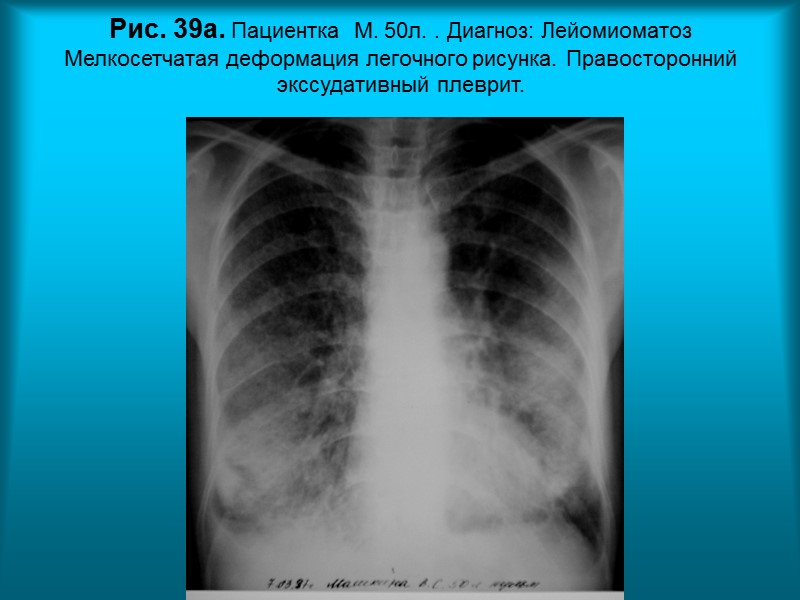

Н.С. Воротынцева. С.С. Гольев Рентгенопульмонология Рис. 39а. Пациентка М. 50л. . Диагноз: Лейомиоматоз Мелкосетчатая деформация легочного рисунка. Правосторонний экссудативный плеврит.

Н.С. Воротынцева. С.С. Гольев Рентгенопульмонология Рис. 39б. Пациентка М. 50л. Диагноз: Лейомиоматоз Мелкосетчатая деформация легочного рисунка. Правосторонний экссудативный плеврит.